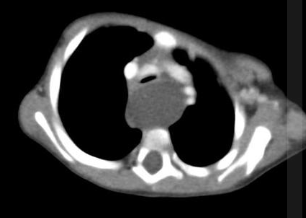

2 anos, masculino

Cisto de duplicação esofágico

Predleção por meninos; diagnosticados na infância

Em geral assintomáticos; podem provocar estridor

Mais comuns no esôfago distal; geralmente não comunicam com a luz do esôfago;

TC: Cisto com densidade de líquido, margens bem definidas que podem realçar com contraste; podem complicar com hemorragia, infecção: nível liquido, espessamento parietal.